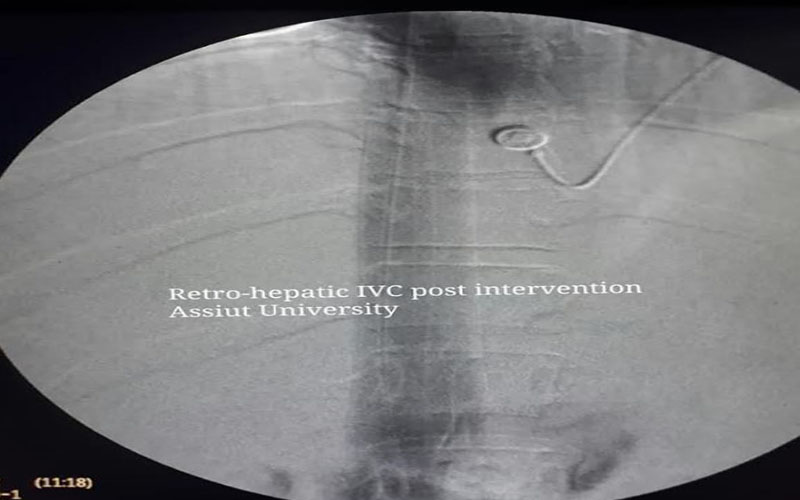

نجح فريق طبي بقسم جراحة الأوعية الدموية بكلية الطب بجامعة أسيوط في إنقاذ حالة تبلغ من العمر 38 عامًا تعاني من تضخم بالكبد والطحال واستسقاء بالبطن ناتج عن ضيق شديد بالوريد الأجوف خلف وأعلى الكبد، وذلك من خلال عمل قسطرة وتركيب دعامتين لتوسيع الوريد الأجوف باستخدام طريقة الدبل برل المتطورة ذات الكفاءة العالية والتي تنفرد بها جامعة أسيوط على مستوى الشرق الأوسط، جاء ذلك تحت رعاية الدكتور طارق الجمال رئيس الجامعة والمشرف على كلية الطب، والدكتور مصطفى سعد رئيس قسم جراحة الأوعية الدموية.

ومن جانبه أشار الدكتور هشام أبو العيون مدرس جراحة الأوعية الدموية ومسؤول الفريق الطبي الخاص بالعملية إلى أن الحالة كانت تعاني منذ عام ونصف من آلام وانتفاخ بالبطن ولم يتم تشخيصها، وعند وصول الحالة إلى المستشفى الجامعي تم عمل أشعة مقطعيه تفصيلية على الأوردة والتي أكدت الانسداد، ثم تم إجراء أشعة تليفزيونية والتي بينت أن أوردة الكبد تعمل بكفاءة الذي يزيد من فرص نجاح القسطرة للوريد الأجوف السفلى، مضيفًا انه تم على الفور تكوين فريق طبي من قسم جراحة الأوعية الدموية وبالتعاون مع قسم الجراحة العامة وتم التدخل وإجراء القسطرة وتركيب الدعامات المدعومة بقساطر الايفوس.

كما نوه الدكتور أشرف النجار المدرس بقسم جراحة الأوعية الدموية ان التدخل باستخدام القسطرة من خلال تقنية الدبل برل بمستشفيات أسيوط الجامعية يعد الأول في صعيد مصر والذي يستخدم في توسيع الوريد الأجوف بالدعامات في علاج هذه النوعية من الحالات وإنقاذها من الفشل الوظيفي في الكبد والذي ينتهي بعمل زرع كبد، مضيفًا أن هذه التقنية تعد مجالًا جديدا لعلاج هذه النوعية من الحالات بتكلفه بسيطة والتي توفر 75% إلى 80% فرق أسعار بين الدعامات الأخرى.